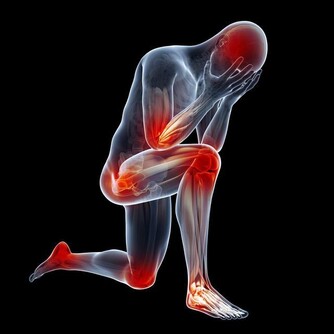

4、全身疼痛——缺乏維生素D 曬太陽不足、或維生素D缺乏的人,就容易引起慢性疼痛,加上維生素D是人體無法自行合成的營養素,補充更為重要。維生素D也是促進骨骼生長、牙齒健全的重要物質。